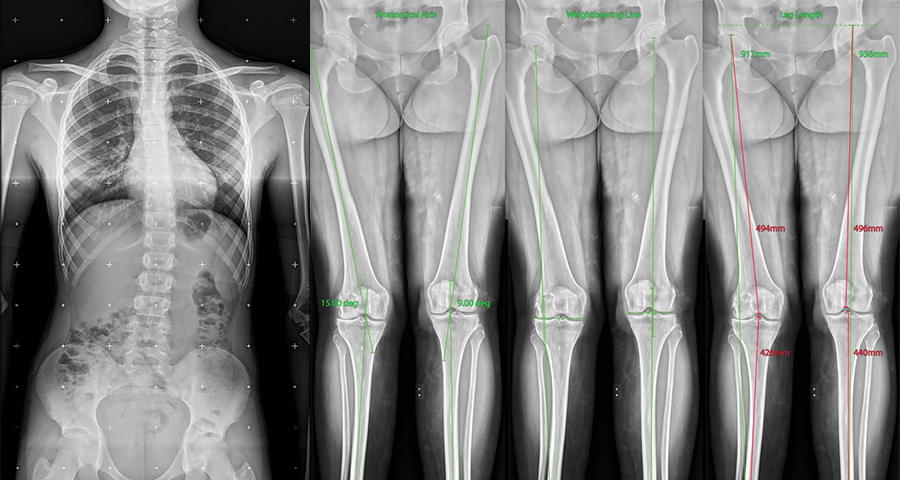

FLFS (Full Leg Full Spine)

This is also called Full Leg Full Spine X-ray system.

This is an integrated system where long segment x-rays of skeletal system are generated.

The x-ray of intended area, viz. whole spine or whole leg are taken together and stitched and printed onto a single film.

This is of great used in pre operative X-rays in certain orthopaedic areas.

We use a dedicated software based measurement system which takes care of most of the needs of orthopaedic surgeon.